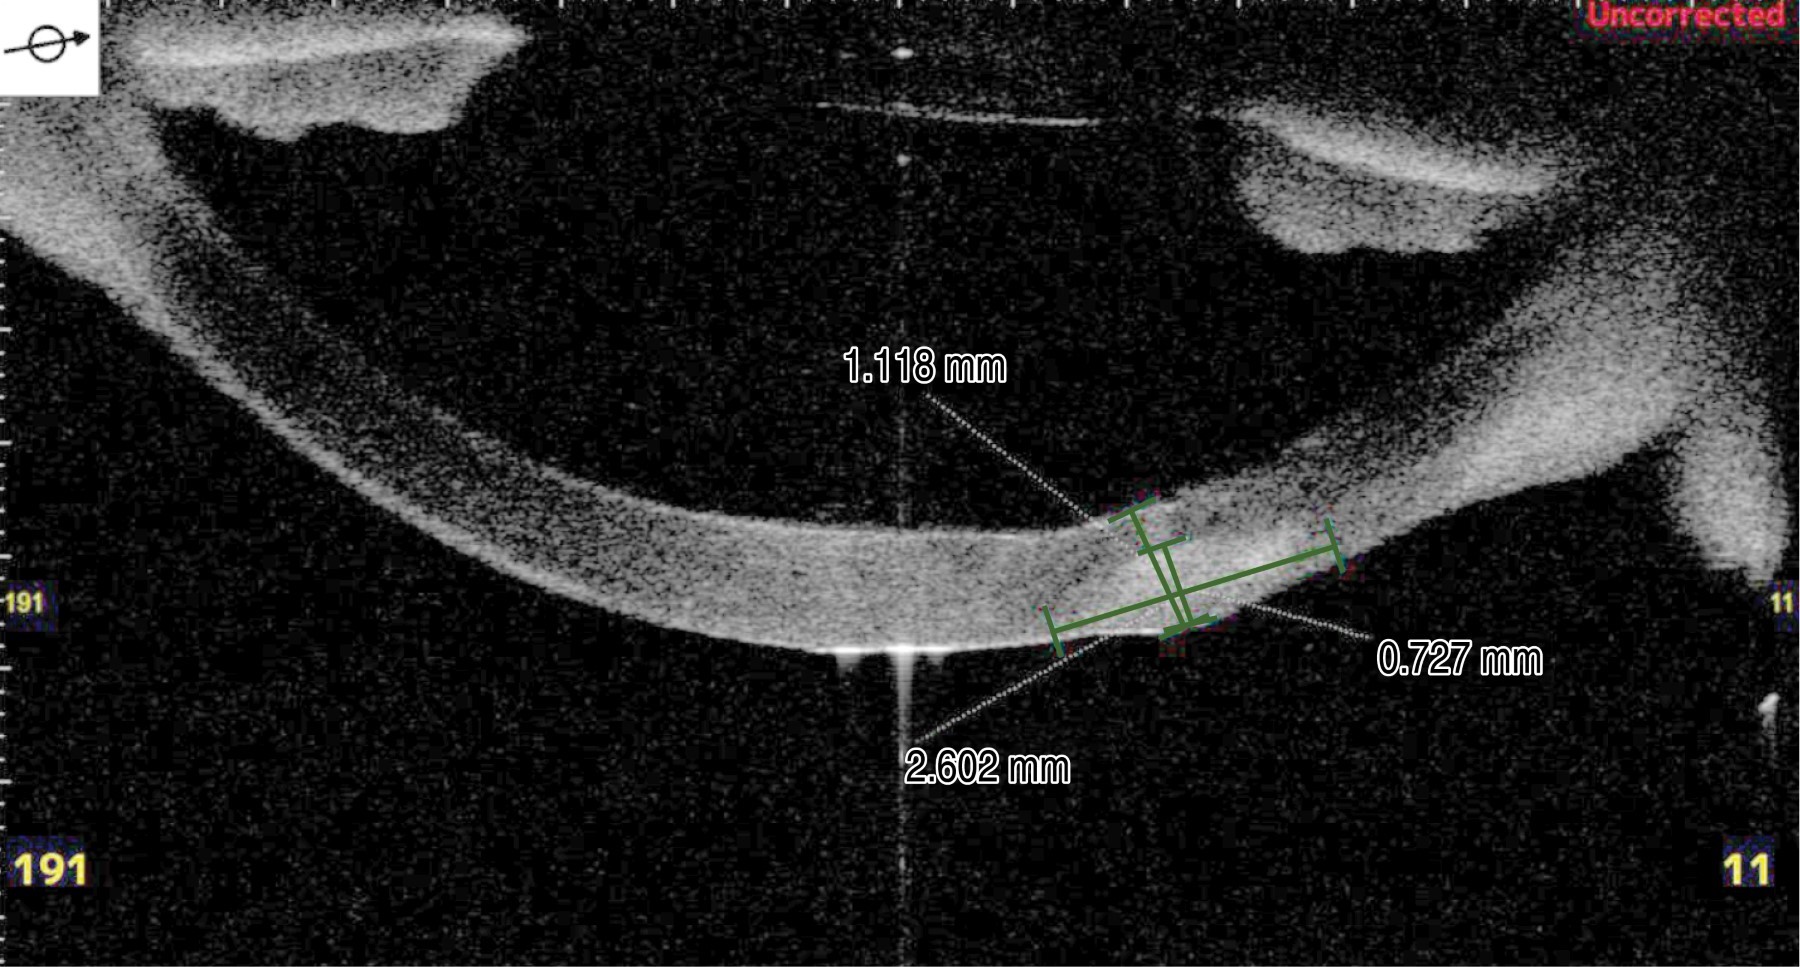

Se realizó tomografía de coherencia óptica de córnea (OCT, por sus siglas en inglés) del segmento anterior donde se identificó cuerpo extraño corneal en estroma profundo, con un grosor corneal total de 1.11 mm y de área afectada una profundidad de 0.727 mm con necrosis activa de 2.6 mm de diámetro (Figura 2).

El postquirúrgico inmediato a las 24 horas, el paciente se refirió estable con disminución significativa del proceso inflamatorio palpebral y síntomas oculares (Figura 3C). En el estudio OCT, a la semana del injerto de tejido corneal, se observó el injerto de 720 micras, limitado a la zona de necrosis secundaria resecada (Figura 5). Con adecuado registro oftalmológico en sus evaluaciones de control (Tabla 1).